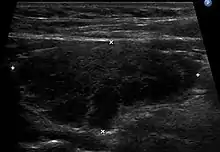

التشخيص عادةً يتمّ من خلال تحديد ارتفاع مستوى الأجسام المضادّة لبيروكسيداز الغدّة الدرقيّة في مصل المريض[9] الأعراض غير الخاصّة الموجودة في مرضى التهاب الدرقيّة المنسوب لهاشيموتو يمكن أن تؤدّي إلى تشخيص خاطئ كأنْ تُشخّص بمرض الإحباط أومتلازمة التعب العام أو اضطراب دوريّة المزاج. في الفحص العياني نلاحظ عادةً وجود انتفاخ قاسي في الرقبة مؤلم عند اللمس[8] والفحص لمستوى الهرمون المحفّز للدرقيّة، وهرمونات الغدّة الدرقية( T3,T4)، والأجسام المضادّة للغلوبين الدرقيّ، والأجسام المضادّة لبيروكسيداز الدرقيّة، والأجسام المضادّة للميكروسومات، ممكن أن يساهم في تشخيص دقيق.[10] التقييم المبكّر للمريض يمكن أن يبرز ارتفاع مستوى الغلوبيولين الدرقيّ بسبب التسمم الدرقي المؤقت؛ وذلك لأنّ التهاب الدرقيّة يسبّب اختلالًا في غلاف الجريبات الدرقيّة التي تخزّن الغلوبيولين الدرقيّ، أمّا الهرمون المحفّز للدرقيّة فيزيد إفرازه من الغدّة النخاميّة في محاولة لتعويض نقص هرمونات الغدّة الدرقيّة(T4). ويُعتقَد أنّ تعرّض الجسم لكميّات كبيرة من أنزيمات الدرقيّة المخزّنة سابقًا يؤدّي إلى تفاقم كسر التحمّل، ممّا يؤدي غلى تفاقم الأعراض لاحقًا. ارتشاح الخلايا اللمفاويّة للأنسجة المرافقة لخلايا الغدّة الدرقيّة يؤدّي إلى وجود تغيير مهمّ نسيجيًّا وهو مركز منتش في العقدّة اللمفاويّة. أحيانًا يمكن أن يظهر مرض التهاب الدرقيّة المنسوب لهاشيموتو على شكل الهوس وهذا ما يُسمّى متلازمة براسادا، نسبةً لعالم النفس أشوك براسادا الذي كان الأول في وصفها .[11]